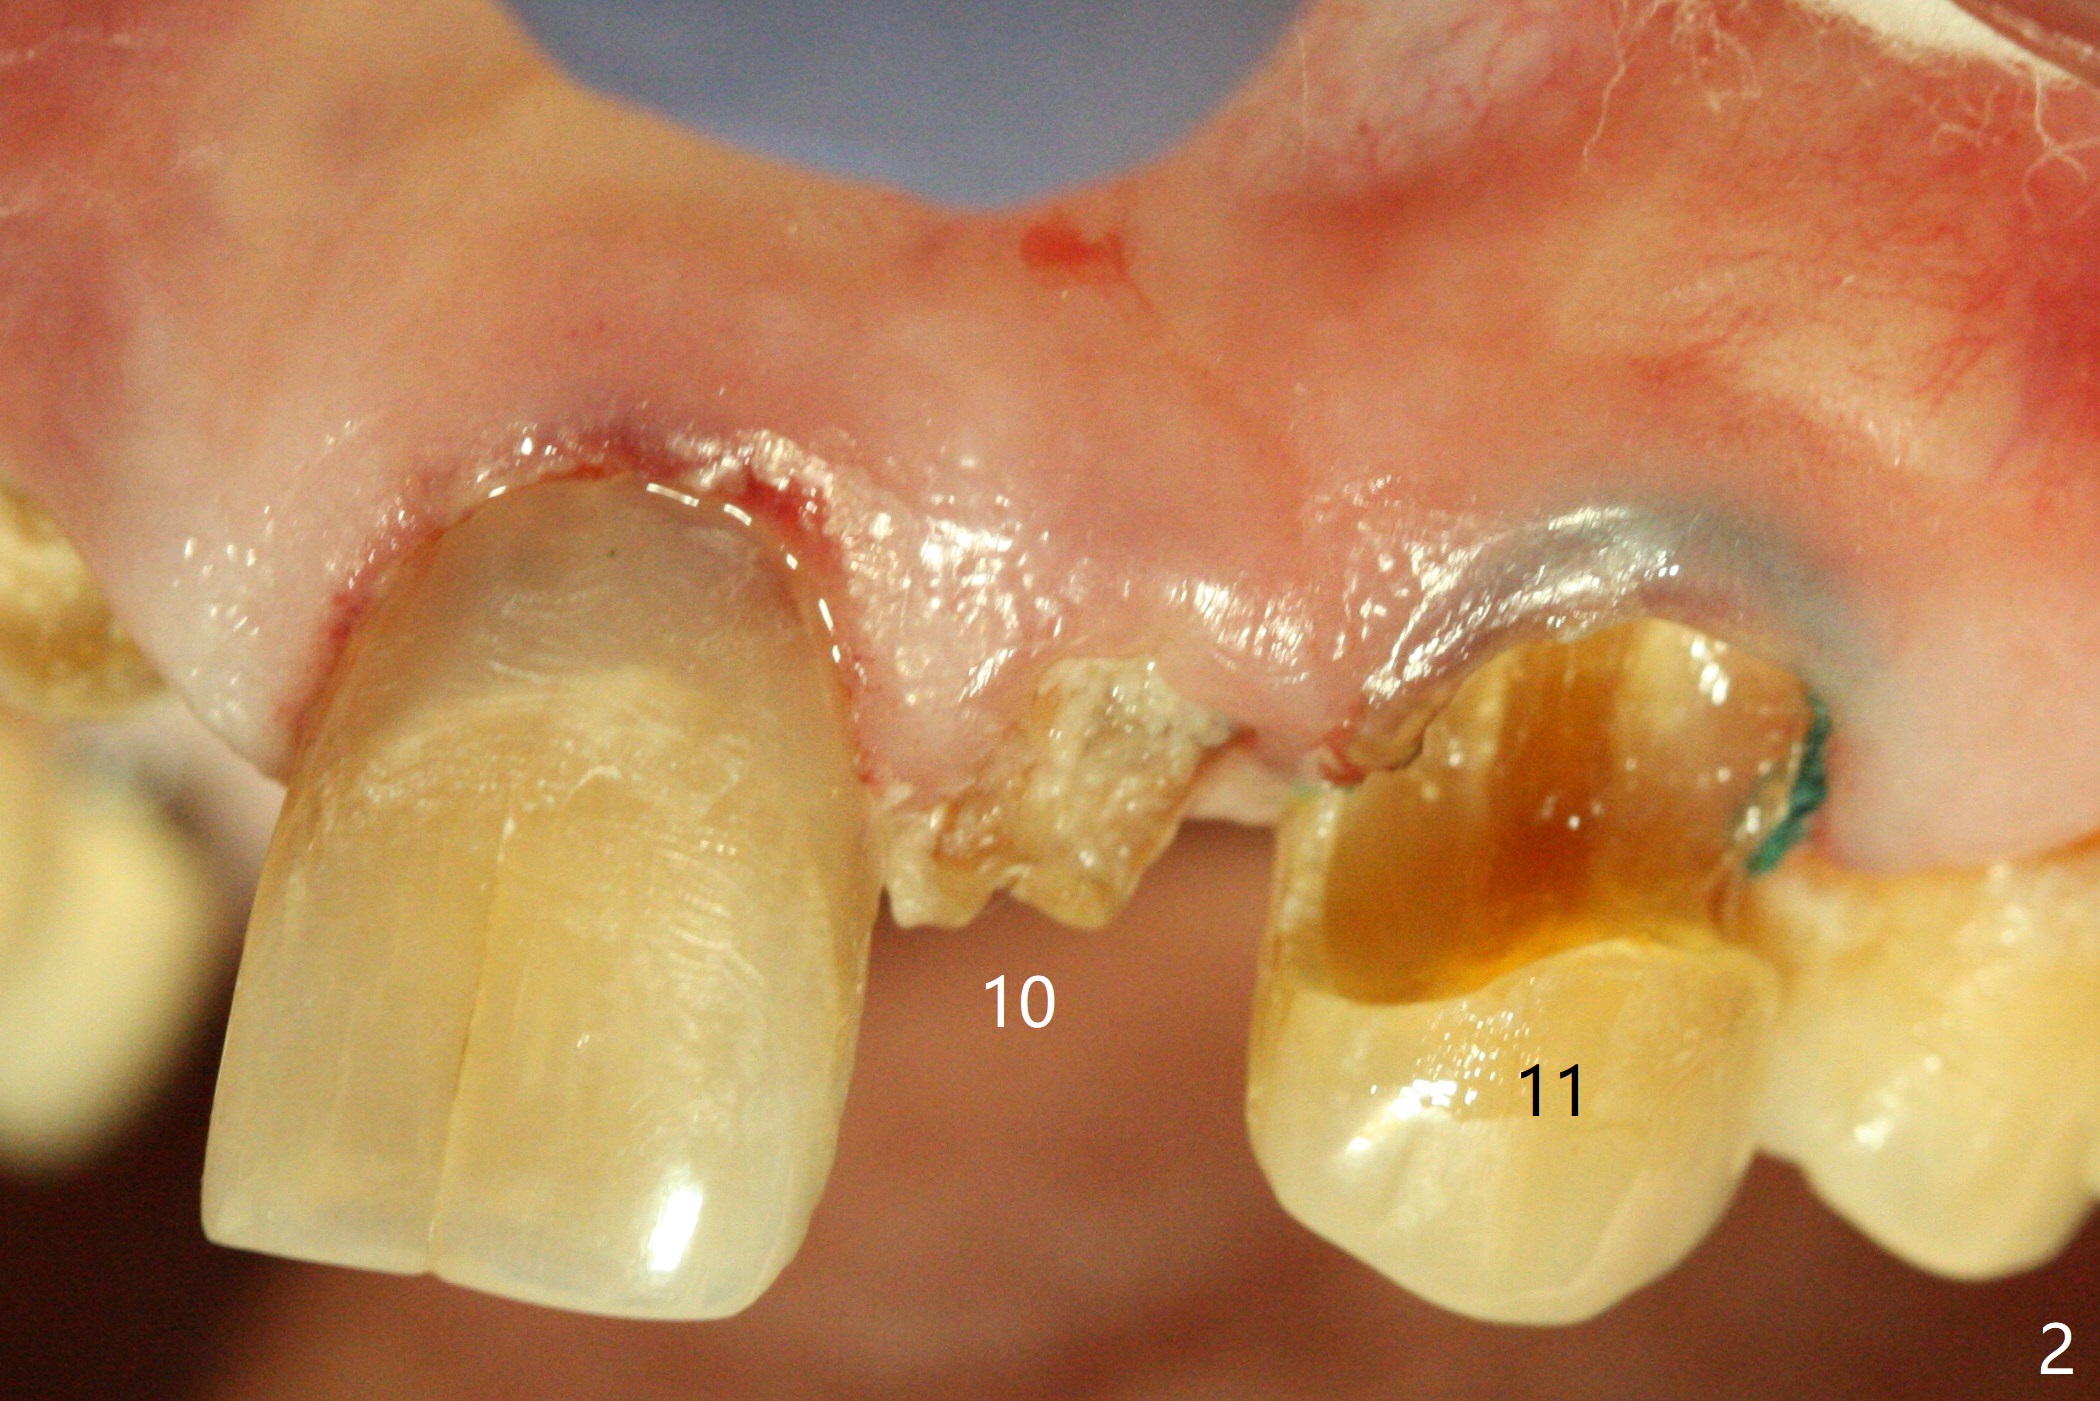

A 89-year-old man has poor dentition (Fig.1). After caries control (Fig.2), implants are placed at #7 and 8 (Fig.3). Because of the buccal plate fracture associated with extracted the ankylosed tooth #8, postop gingival recession occurs (Fig.3 arrow). To prevent the complication, socket shield will be performed if extraction of the tooth #10 turns out to be difficult. A 2.5 or 3x16 mm 1-piece or 3.5x13 mm/3.8x15 mm 2-piece implant will be attempted to be placed. Take preop photos to show #7 and 8 crowns and #10 residual root . Incision may be made to expose the labial crest to make sure that the the remaining labial portion of the root is caries free after extraction with sectioning.